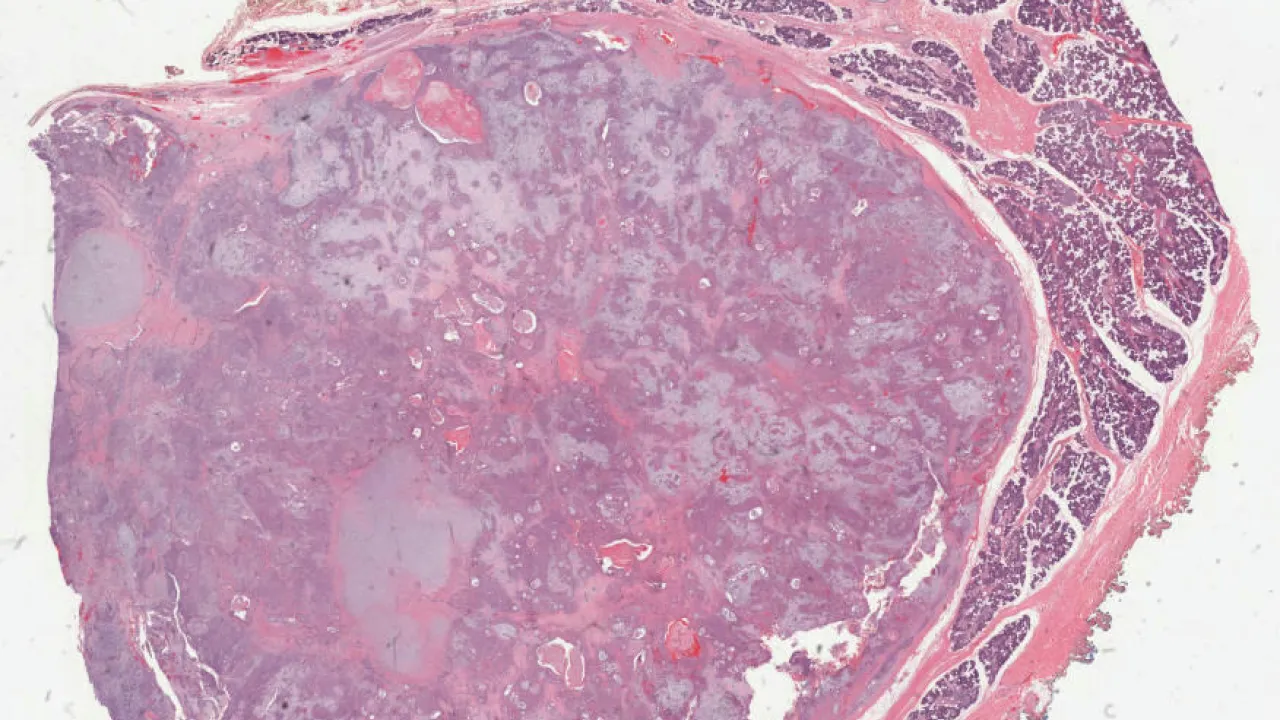

Testis, Mixed germ cell tumour, B-HCG stain